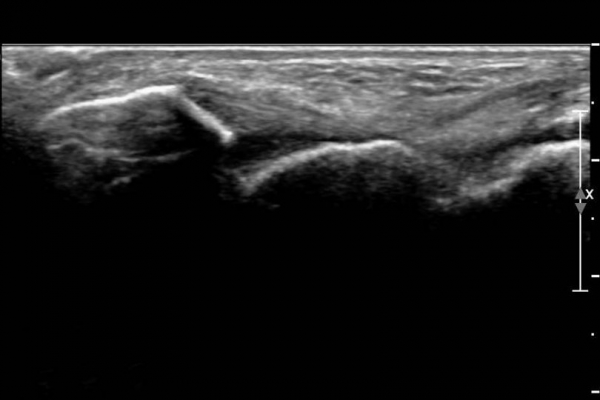

ÃÊÀ½ÆÄ ¼Ò°ß :  ¹ß¸ñ ¾Õ Á¾´Ü¸é°Ë»ç¿¡¼­ ¹ß¸ñ°üÀý³»  ¾à°£ÀÇ ¼ö¾×Àú·ù°¡ °üÂûµÊ(»çÁø 1).